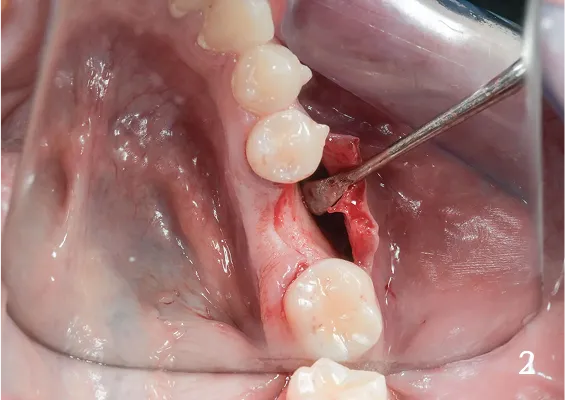

ODBUDOWA UBYTKU PO USUNIĘCIU ZĘBA - SOCKET PRESERVATION

To prosta, szybka i bezpieczna technika odbudowy kostnej zębodołu po ekstra-kcji zęba. Znana wcześniej, lecz opisana dopiero w ramach międzynarodowego konsensusu z 2010 roku (prof. Lindhe, prof. Araujo)

Zabieg odbudowy zębodołu powinno się wykonać możliwe jak najszybciej po usunięciu zęba. Jego celem jest odbudowa naturalnej objętości kości w miejscu utraconego zęba, a następnie szybkie wprowadzenie implantu. Najlepsze rezul-taty uzyskuje się przy zastosowaniu biomateriału w formie bloczków kolageno-wych lub granulatu, które dają trwałe efekty odbudowy oraz optymalną funkcję i estetykę odtworzonych koron zębów na wszczepionym implancie.

Materiał kościotwórczy występuje zazwyczaj w formie granulatu o różnej grubości drobin. Może być materiałem odzwierzęcym, syntetycznym lub homogennym. W Polsce statystycznie najczęściej używane są materiały pochodzenia odzwierzęcego pozyskane od zwierząt kręgowych. Usypany do ubytku ma on za zadanie stworzenie mineralnego szkieletu dla odbudowującej się tkanki kostnej. W trakcie jej tworzenia materiał ulega integracji z tkanką pacjenta. Membrana kolagenowa to cienka błona w formie prostokąta o różnych wymiarach, która ułożona w miejscu odbudowy ma za zadanie izolację nowo tworzącej się kości w ubytku od wnikania włóknistej tkanki podśluzowej, która zaburza proces osteogenezy.

Bloki kolagenowe używane są najczęściej do odbudowy geometrycznych, trójwymiarowych ubytków kostnych, których doskonałym przykładem jest zębodół po ekstrakcji zęba. Jest to jeden ze sposobów na procedurę „socket preservation”, czyli natychmiastową lub wczesną odbudowę zębodołów poekstrakcyjnych dla osiągnięcia optymalnych efektów estetycznej odbudowy protetycznej koron zębów na implantach. Membrana kolagenowa to cienka błona w formie prostokąta o różnych wymiarach, która ułożona w miejscu odbudowy ma za zadanie izolację nowo tworzącej się kości w ubytku od wnikania włóknistej tkanki podśluzowej, która zaburza proces osteogenezy.